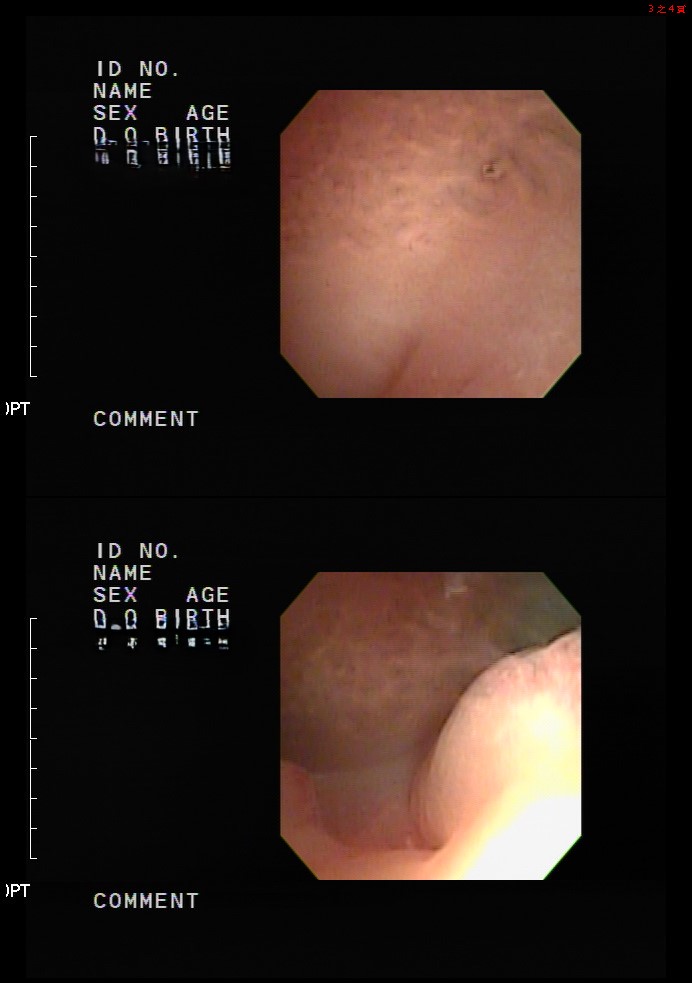

小美決定尋求幫助, 於是來到了我們的中山醫學大學附設醫院生殖醫學中心。經過詳細的檢查,我們發現了小美子宮內膜息肉以及維生素D缺乏, 這些是影響她懷孕的關鍵因素。

後來,我們為她制定了客製化的治療計劃,包括息肉切除手術和維生素D補充來進行卵子培養。 手術後,小美感覺到生活慢慢回到正軌。